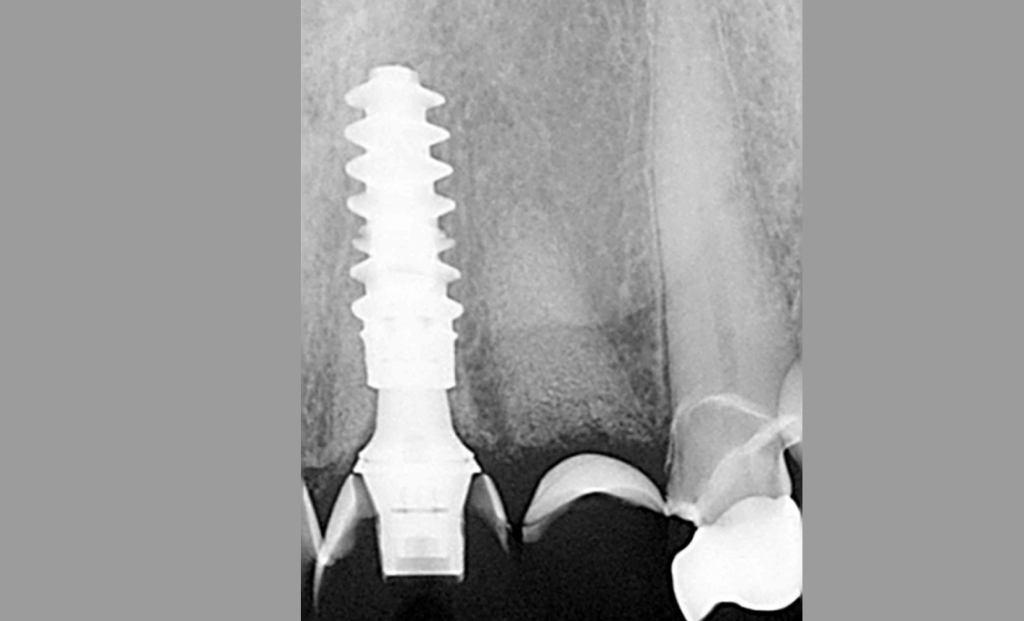

Одиночная имплантация. Клинический пример

Выбор одинарного абатмента был упрощен благодаря семейству ti-base, принятому большинством производителей имплантатов. Эти абатменты имеют ретенционную часть, к которой экстраорально прикрепляются изготовленные в лаборатории протезы. Абатменты бывают разного диаметра и высоты десневой манжеты. Выбор правильной высоты и диаметра должен осуществляться клинически. Проблема стандартизации этой очень простой процедуры иллюстрируется рентгеновским изображением на рис. 1.

Этот пациент обратился ко мне с жалобами на сильную боль, покраснение и отек вокруг только что установленной коронки на имплантате. В анамнезе было следующее: был снят аналоговый оттиск с уровня имплантата и отправлен в лабораторию для изготовления коронки. У лаборанта не было указаний относительно расположения шейки имплантата по отношению к мягким тканям и кости.

Была выбрана самая короткая высота десневой манжеты (GH), так как она является наиболее безопасной с эстетической точки зрения, поскольку металлическая кромка не будет видна над десной. При доставке коронки на имплантат стоматолог столкнулся с трудностями при «посадке» коронки на абатмент.

Коронка была установлена со значительным сопротивлением для достижения необходимого значения торка. Ущемление твердых и мягких тканей из-за очень острого профиля выступа вызывает давление на кость, что приводит к некрозу и, в конечном итоге, к потере маргинальной кости в этой области. Чтобы избежать подобных осложнений, необходимо выбирать правильный абатмент.

На основе ОПТГ, сделанного после установки или имплантата (рис. 2), стоматолог может выбрать подходящую высоту десневой манжеты для абатмента и направить техника, предоставив рентгеновский снимок и/или спецификацию формирователя десны. Большинство систем имплантатов имеют синхронизированные формы и контуры хирургических абатментов и компонентов протеза.